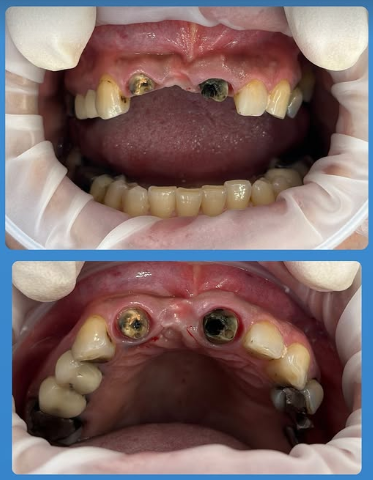

- بررسی وضعیت استخوان و لثه: برای اطمینان از موفقیت ایمپلنت یک روزه در مشهد، پزشک با استفاده از تصاویر رادیوگرافی یا اسکن سهبعدی، تراکم و سلامت استخوان فک را بررسی میکند. در این مرحله مشخص میشود که آیا بیمار شرایط لازم برای کاشت فوری ایمپلنت را دارد یا نیاز به درمانهای تکمیلی مانند پیوند استخوان وجود دارد.

- کاشت پایه ایمپلنت: در این مرحله، جراح دندانپزشک پایه تیتانیومی ایمپلنت را در داخل استخوان فک قرار میدهد. این فرآیند تحت بیحسی موضعی انجام میشود تا بیمار دردی احساس نکند. پایه ایمپلنت به گونهای در فک جایگذاری میشود که پایداری اولیه لازم را داشته باشد و بتواند روکش موقت را تحمل کند.

- نصب روکش موقت: پس از کاشت پایه ایمپلنت، یک روکش موقت روی آن قرار میگیرد تا بیمار بتواند بلافاصله از ظاهر و عملکرد دندان جدید خود بهرهمند شود. این روکش معمولاً از مواد سبک ساخته میشود تا فشار زیادی به ایمپلنت وارد نشود و روند جوش خوردن استخوان بهدرستی طی شود.